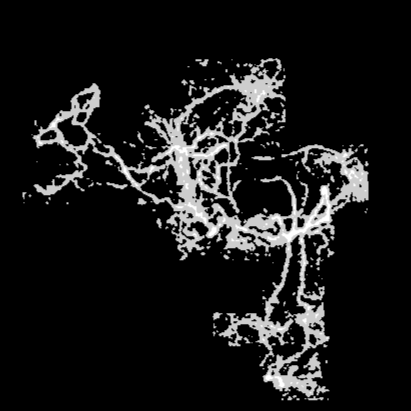

Knowing that an OCTA image has a scale of and that each OCTA image contains pixels, we find the size of one pixel to be 0.154 . The original image after the ”Image Processing” phase focuses on the blood vessel area, represented by the white pixels. It indicates the size of the active mCNV lesion. The internal black areas show parts of the object where the blood vessel is missing. Figure 8 illustrates a structure similar to a sponge.

To calculate the total area, we need to pass the output image from the ”Image Processing” phase through another operation, Region Fill, to fill in the black missing sections from the initial binary image. After applying this filter, the total vessel area will be larger than the mCNV area: .

Feature combination is then applied to compute the Vessel Density, which is the ratio of the mCNV Area to the Total Area: .

We illustrate here how the processing steps lead to the binary image, which contains essential information about the blood vessels. Fig. 9 shows the steps involved in the Data Cleaning phase and Otsu Thresholding.

Fig. 10 presents the image processing techniques and their outcomes at each iteration. The grayscale images progressively approach a binary representation, as seen after the application of multiple binarization techniques. The salt and pepper filter removes part of the noise. In the final image, all components are colored in a way that highlights the principal component. Any remaining noise is removed in Fig. 11, which also shows the result after applying region filling techniques.